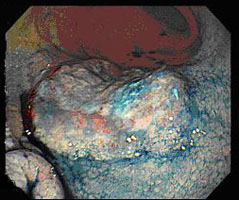

特に近年は処置具を含めた内視鏡機器の発展により、粘膜下層剥離術(ESD)とよばれる内視鏡的治療が広くなされるようになりました。病変を内視鏡直視下に観察して、切除範囲を決めるマーキング、粘膜下層への局注液注入、周辺切開、剥離の手順で病変を一括して切除、回収します。なお臨床試験として近年では粘膜内癌で潰瘍のないものであれば大きさは制限なく、また粘膜下層浅層への病変や、潰瘍廏痕合併の病変などは大きさを限定して施行しています。

早期胃がんの内視鏡的粘膜下層剥離術(ESD)の実際

最終診断:Gastric cancer pType 0 IIc T1(M) tub1 INFα, ly0, v0